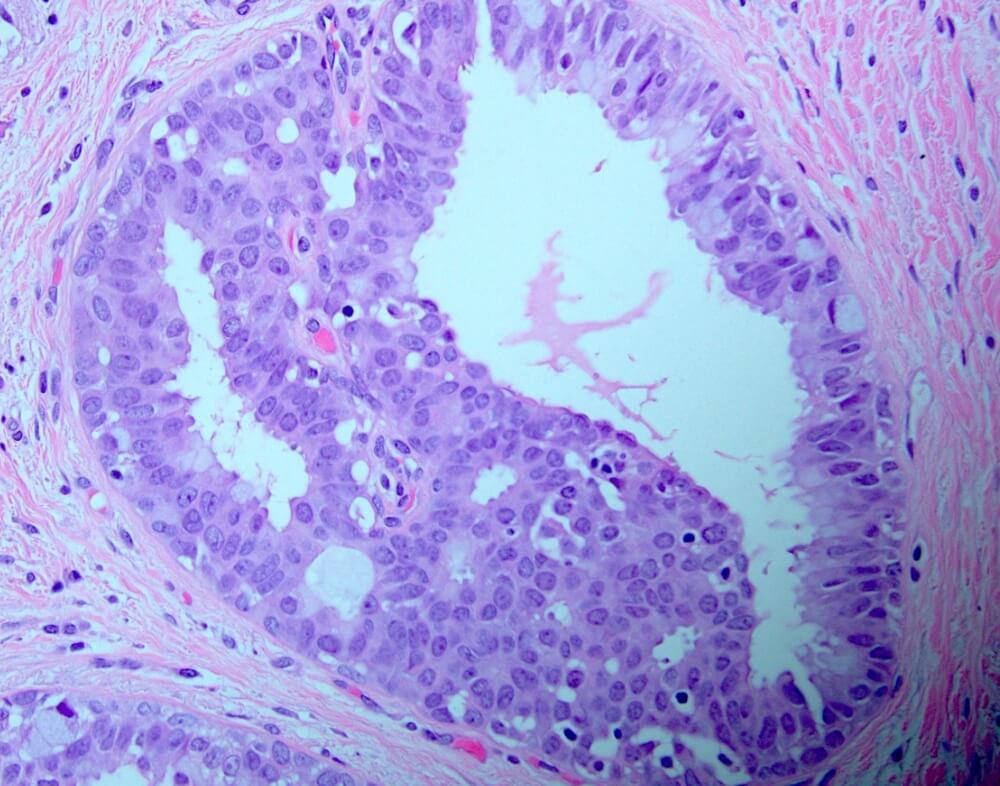

Η αύξηση στον αριθμό των στιβάδων και στον αριθμό των κυττάρων ονομάζεται υπερπλασία.

Όταν η υπερπλασία αφορά κύτταρα με φυσιολογική εμφάνιση και αρχιτεκτονική ονομάζεται απλή υπερπλασία και δεν συσχετίζεται με κίνδυνο ανάπτυξης κακοήθειας.

Αντίθετα, όταν συνοδεύεται από αλλαγή στην φυσιολογική εμφάνιση και αρχιτεκτονική των κυττάρων χαρακτηρίζεται ως άτυπη υπερπλασία και συσχετίζεται με κίνδυνο ανάπτυξης κακοήθειας.

Η άτυπη υπερπλασία διακρίνεται σε άτυπη λοβιακή υπερπλασία και σε άτυπη υπερπλασία των πόρων.

Η άτυπη υπερπλασία των πόρων επίσης μπορεί να αποτελεί μικροσκοπικό εύρημα σε χειρουργικό παρασκεύασμα ή σε παρασκεύασμα βιοψίας με βελόνη.